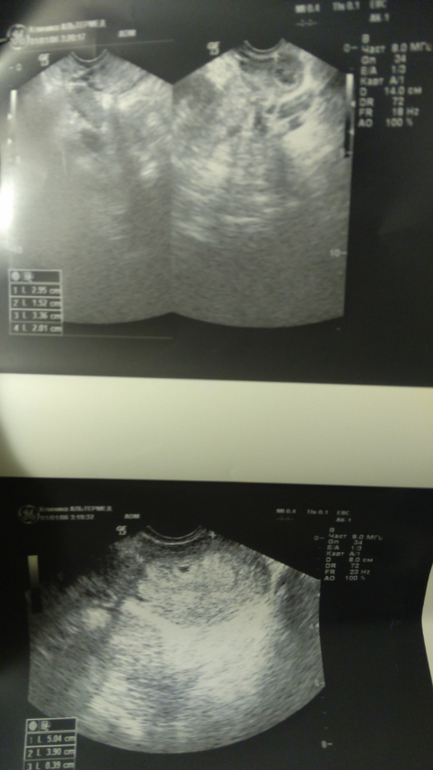

Вопросы про УЗИ, обследования и анализы: что, где, как, когда?Девочки, привет. Сходила на УЗИ сегодня, поставили угрозу, т.к. низко расположено плодное яйцо. И есть гематомы из-за отслойки хориона. Одно плодное яйцо 4 мм.

А что там еще отслаиваться может? может я что-то перепутала, но она сказала, что из-за этого гематомы небольшие

Отслаиваться может само плодное яйцо, из-за этого могут быть гематомы. Вы себя вообще как чувствуете?